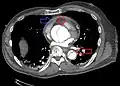

Computed tomography

Computed tomography angiography is a fast, non-invasive test that gives an accurate three-dimensional view of the aorta. These images are produced by taking rapid, thin-cut slices of the chest and abdomen, and combining them in the computer to create cross-sectional slices. To delineate the aorta to the accuracy necessary to make the proper diagnosis, an iodinated contrast material is injected into a peripheral vein. Contrast is injected and the scan performed using a bolus tracking method. This type of scan is timed to injection to capture the contrast as it enters the aorta. The scan then follows the contrast as it flows through the vessel. It has a sensitivity of 96 to 100% and a specificity of 96 to 100%. Disadvantages include the need for iodinated contrast material and the inability to diagnose the site of the intimal tear.

CT with contrast demonstrating aneurysmal dilation and a dissection of the ascending aorta (type A Stanford)